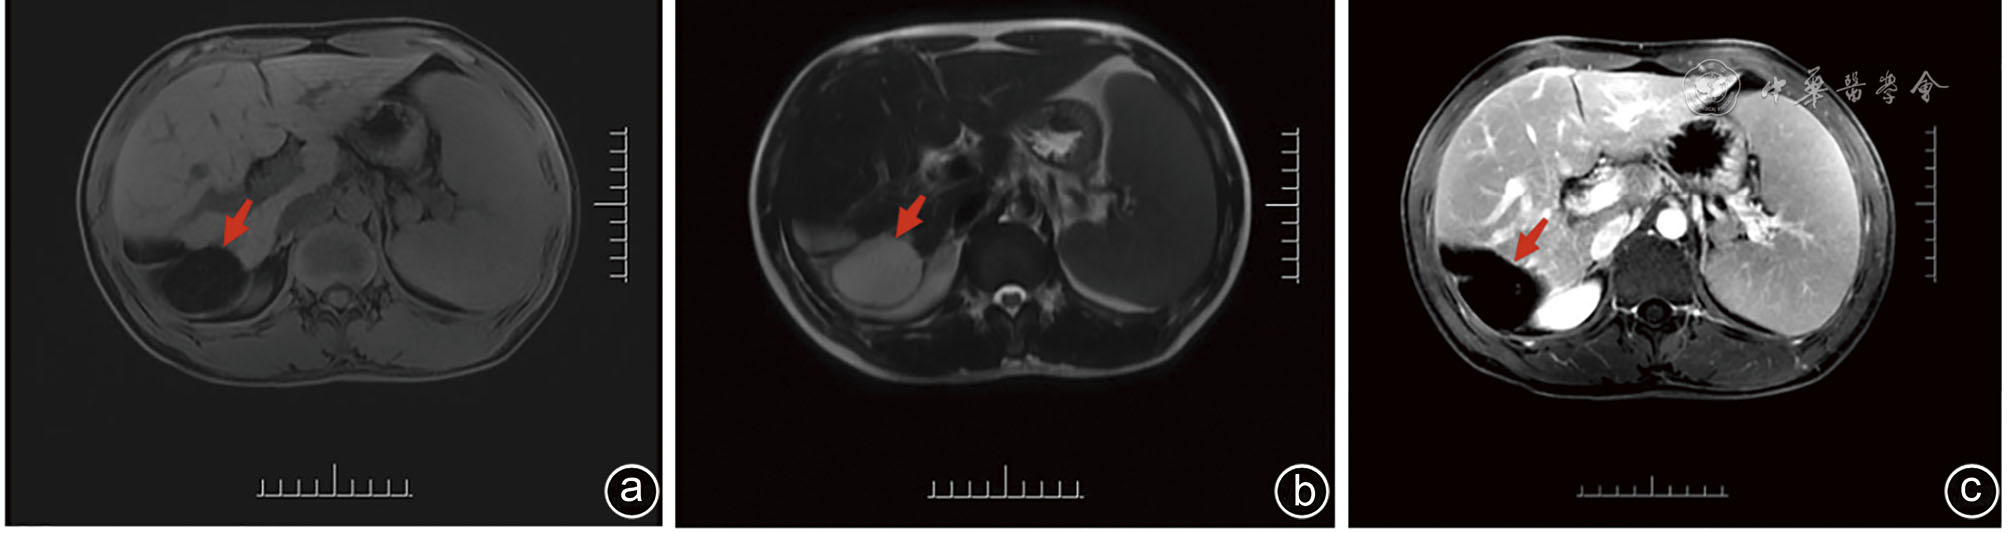

图1 一例肝右后叶包膜下脂肪瘤患者术前腹部CT图像 注:a为平扫;b为动脉期;c为静脉期;肝右后叶包膜下见一片状脂肪密度影,增强后无强化(红色箭头所示)

Clinical data of a 32-year-old male patient with hepatic lipoma admitted to Department of Hepatobiliary and Pancreatic Surgery of the Second Affiliated Hospital of Kunming Medical University in November 2023 were retrospectively analyzed. He was hospitalized due to a liver-occupying mass during physical examination. Physical examination revealed nontender abdomen. Complete blood count, blood biochemistry, coagulation function and AFP level was detected normal, while CA50 level was increased. Abdominal ultrasound showed hyperechoic area in the space between liver and kidney. Contrast-enhanced ultrasound revealed that the lesions showed uneven and slight hypoenhancement in the early stage and hypoenhancement in the late stage. Abdominal contrast-enhanced CT showed subcapsular fat density shadow in the right posterior lobe of liver. MRI showed round-like long T1 and long T2 signal shadows in the subcapsular area of the right posterior lobe, without enhancement. Spleen was significantly enlarged. No abnormality was found in parenchymal signals, and no enhancement was observed. MRCP showed no dilatation was seen in the intra-and extra-hepatic bile ducts. Literature review about liver lipoma was conducted and the experience of diagnosis and treatments was summarized.